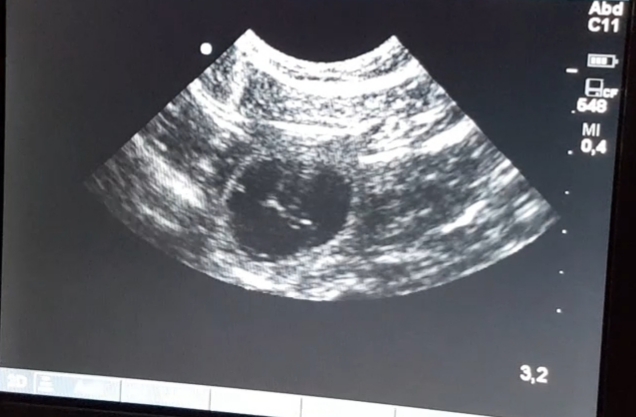

Am 22. Tag sind die Embryonen sichtbar. Der Herzschlag kann zur Diagnose der Trächtigkeit herangezogen werden. Anstrengende Aktivitäten sind jetzt zu vermeiden. Die Proteinzufuhr im Futter kann erhöht werden. Hierfür eignet sich sehr gut die Gabe von Welpenfutter. Zu diesem Zeitpunkt kann mit einer Ultraschalluntersuchung der Zustand der Trächtigkeit festgestellt werden.

Ich konnte es nicht aushalten und habe mein Glück bereits am Donnerstag, 11.4. versucht... und siehe da. Juheeeyyy